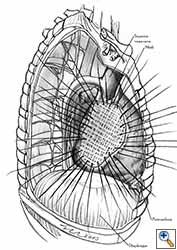

Pericardial reconstruction is indicated after extrapleural pneumonectomy for diffuse malignant pleural mesothelioma. Right-sided pericardioplasty is performed to prevent cardiac dislocation as discussed above. Left sided pericardial defects that result after extrapleural pneumonectomies are large and there is no risk of cardiac strangulation, but reconstruction is recommended in order to prevent constrictive epicarditis (Figure 3) [4].

Video 1 depicts a pericardial reconstruction with Marlex after a right completion pneumonectomy with pericardiectomy for lung adenocarcinoma (see also Figure 1). The technique of pericardial reconstruction after the resection of invasive mediastinal tumours is illustrated in Figures 8a-c). Video 2 depicts a pericardial reconstruction with Mersilene mesh after the resection of a malignant thymoma invading the anterior pericardium (see also Figure 4b). The technique of right pericardial reconstruction after extrapleural pneumonectomy is illustrated in Figures 9a and 9b). Video 3 depicts a pericardial reconstruction using Gore-Tex Dual Mesh after a left extrapleural pneumonectomy (see also Figure 3). Care must be taken to prevent constriction (Figure 10).